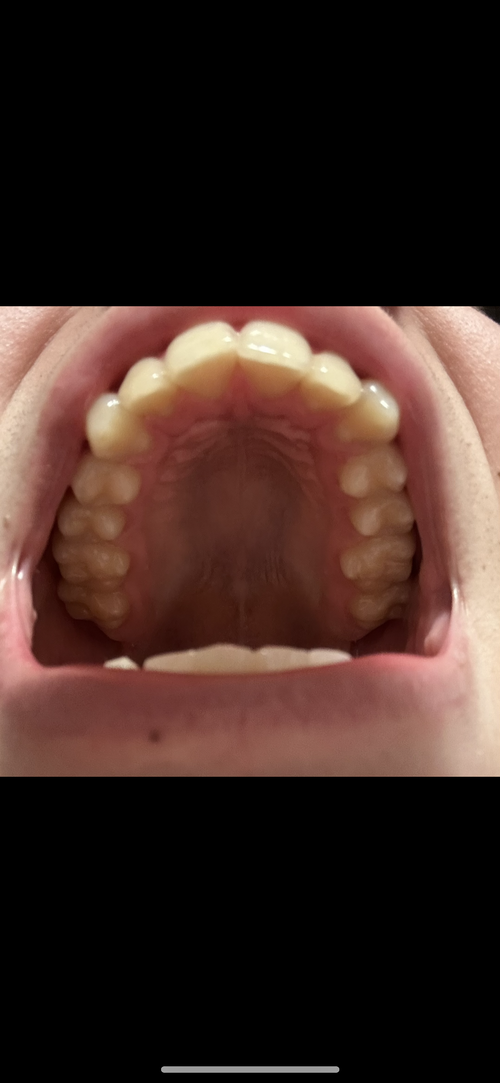

I think I hit a few of the criteria.

bad class 2, Okayish gonion width without needing implants and the sfs 0 gingival and upper incisor show smile.

I have a borderline short face as you can see by my scans.

I have a long ramus and well rotated jaw, which I think fits the criteria, although I have a class 1 dental occlusion, we’re going to decompensate my teeth as much as possible, so I can get a bigger movement.

Do you think a small bit of downgrafting is necessary? I’m also gonna add height and width to my chin with custom genio.

My surgeon is gonna do roughly a 12mm BSSO and 5mm Lefort 1. Haven’t decided genio movements yet.

I don’t have great gonion flare, however I’m just gonna chew and build my masseters for lower third width.

Thoughts on everything? @lurking truecel